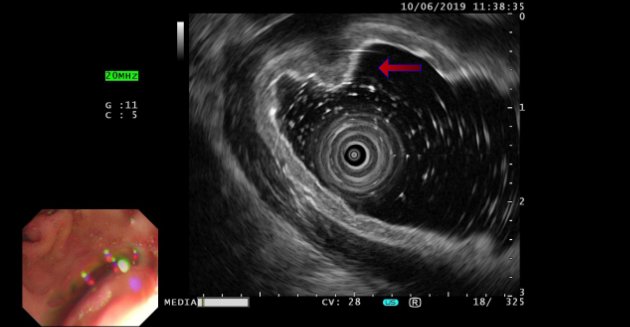

2019?, ??? ??? ???? ??? gastric antrum?? lesser curvature? submucosal bulging mass? ?????? submucosal ectopic pancreas? ???????. (?? 2)

Gastric window? ?? ?? ??? ??:

??? ???(instant gastrointestinal ultrasound aid) 500mL? ?? ???? ?? ? ??? ??? ?????. Gastric wall? ??? ???? ?? ??? ???? ?? ??????, Gastric antrum? lesser curvature? submucosal layer??? ? 1.36cm├Ś0.87cm ??? ?? ??? hypoechoic mass? ???????. ??mass? ????? ????? ????, ???? ?? ???? ???????.

???, mass? ??? ???? ?? ??? ?????, mass ????? ???? echogenicity ? ???????.(?? 3).